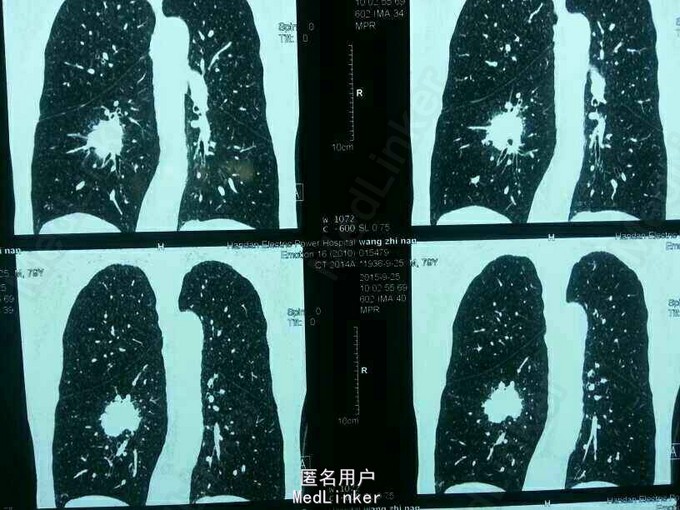

胸部占位病变

患者无任何临床体征,单位体检发现。男,79岁